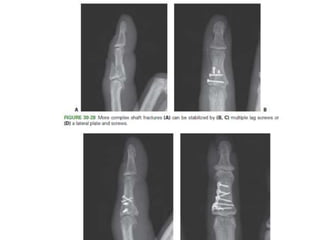

• Unstable shaft fractures

– CRIF – K wiring

– ORIF – Lag screw fixation – if rotational instabiity.

– Plate and screw fixation – if axial instability.

• #84 Figure 30-51 More complex fractures of the shaft can be well stabilized by (B) lateral plating. Specific care should be taken to (C) contour the plate meticulously to fit the cortex and to place the hardware in (D) the true midlateral position.